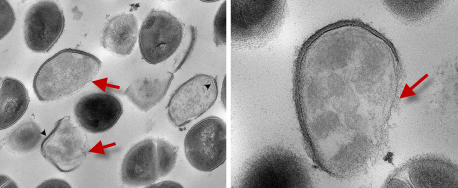

• Бактерицидное действие  – разрушение мембран бактерий, что приводит к их гибели.

• Мембрана бактерий состоит из  пептидогликанов  и аминокислот и имеет  отрицательный заряд

• Положительно заряженные ионы  Ag+ взаимодействуют с мембраной, адсорбируясь на ней

• Это блокирует способность мембраны передавать кислород внутрь клетки, вызывая "удушье" бактерии

• Повышение осмотического давления, что приводит к разрушению клеток

• Разрушение  ДНК, предотвращающее размножение бактерий